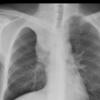

Silhouette sign

RML collapse

(see previous image)